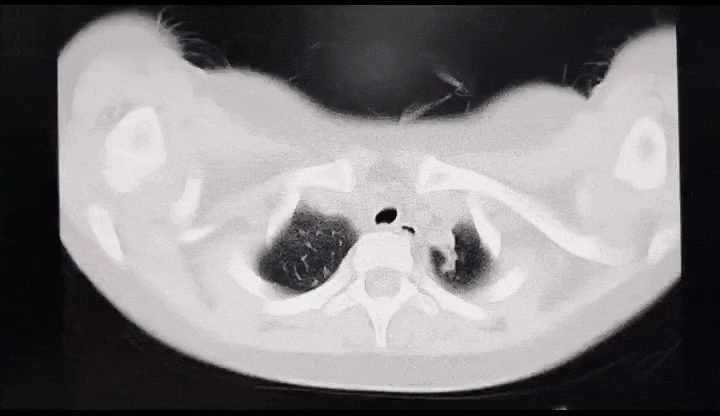

支原体肺炎的影像学表现。图源:深圳卫健委有的支原体肺炎患儿,肺部影像上显示有一片白色,大多是一个肺叶或一个肺段感染所致,主要是由于气道阻塞物或肺内炎性渗出引起的,但其他的肺叶大多数都是正常的,这和医学上所说的“白肺”是两个概念。